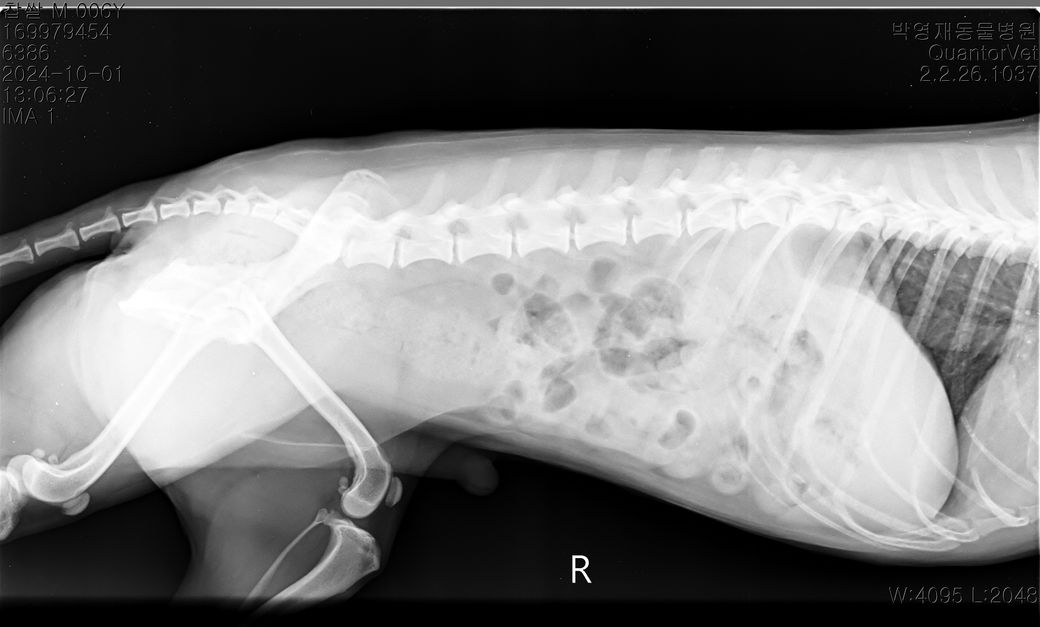

현제 6살 3개월 남자 중성화 되어있는 5.6kg 비숑 입니다,

1살 6개월쯤 뛰다 미끄러져 병원 내원 했을때 십자인대 부분단열 의심.탈구 1기 진단 받았고

3주전쯤 흥분해 뛰다 턴하면서 악소리를 크게지르고 주저 앉았다 다리를 들고 있었고 수분뒤엔 다시 잘 걸었습니다. 다음날 병원 내원 엑스레이,촉진상 근육이 좋아서 탈구도 약간있고 십자인대 가 좀 좋진 않지만 당장 수술할정도는 아니라 들었습니다. 근데 그뒤로 집에서 걷다가도 밖에서 뛰다가도 하루 한두번씩 그래요.